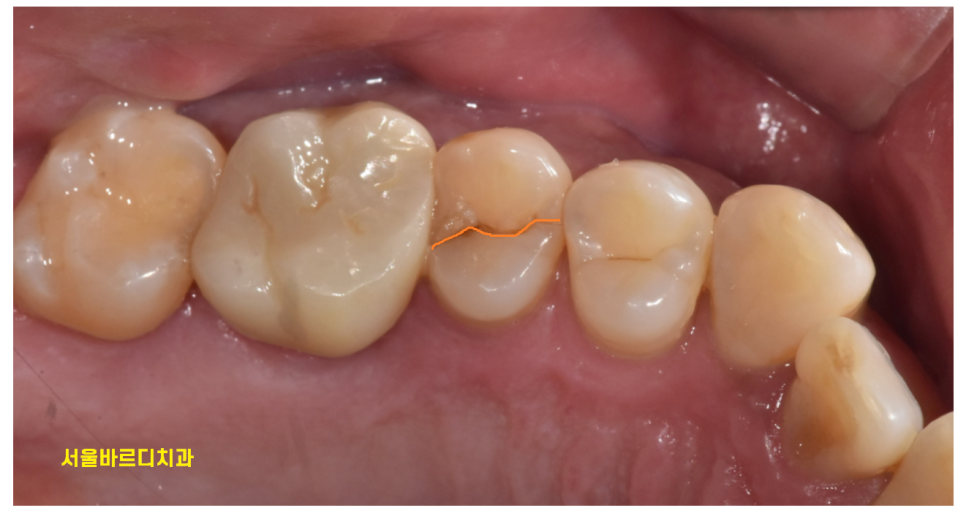

정확히 절반으로 어금니 쪼개짐

발생했습니다.

확대해서 보면

이런 모습이죠

하지만 오늘처럼 치아가 수직으로

도끼로 나무를 내려찍은듯한 형태인 경우

살리기가 힘듭니다.